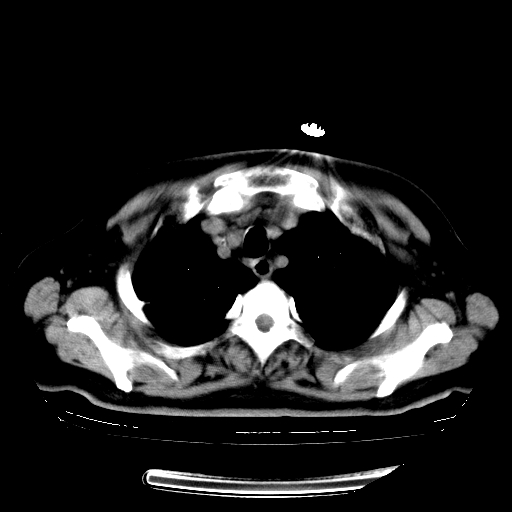

标题: CT23067:女,70岁,咳嗽、咳痰一个月,低热一周。 [打印本页]

女,70岁,咳嗽、咳痰一个月,低热一周。

1.左上肺结核,部分纤维化。右肺中下叶部分肺不张,内见液化、坏死及点状钙化,右中下叶支气管壁增厚、管腔狭窄,见多个点状钙化,结合临床考虑支气管内膜结核,建议痰检查抗酸杆菌并参考血沉。两肺多个小圆点状高密度灶,境界模糊,多考虑结核肺内播散。但本人年龄较大首先应支气管镜检以除外右肺癌。

2.胸主动脉夹层。